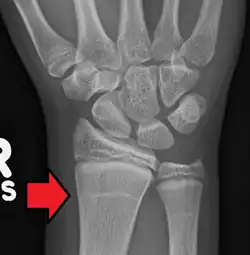

Harris lines are stress indicators on the skeleton that form due to malnutrition, disease, or other stress factors during childhood.[8] During this time, bone growth is temporarily stopped or slowed down but bone mineralization will continue. Once the stress has decreased or stopped, bone growth will resume, which results in a line of increased mineral density that can be seen in radiographs. If there is no recovery from stress, no line will be formed.[5][9]

Ameen et al. (2005) studied the incidence of Harris lines in medieval populations from Berne, Switzerland. the scholars from the University Hospital of Berne collected radiographs of the tibia from 112 well-preserved skeletons that lived during the 8th-15th centuries. They also compared their results with the radiographs of 138 living patients in the same geographic region. They found evidence of Harris lines in 88 of the 112 (80%) medieval skeletons and in 28 of 138 (20%) of the living individuals. In both populations, Harris lines were found at age 2 and between ages 8 and 12. The occurrence of Harris lines was associated with degenerative bone disease, trauma, osteoporosis, peripheral vascular diseases, rickets, rheumatoid arthritis, and bony deformities. The authors concluded that the medieval populations in Switzerland probably experienced difficult living situations and poor hygienic conditions and the Harris lines in children of the population reflected poor care and neglect.[10]